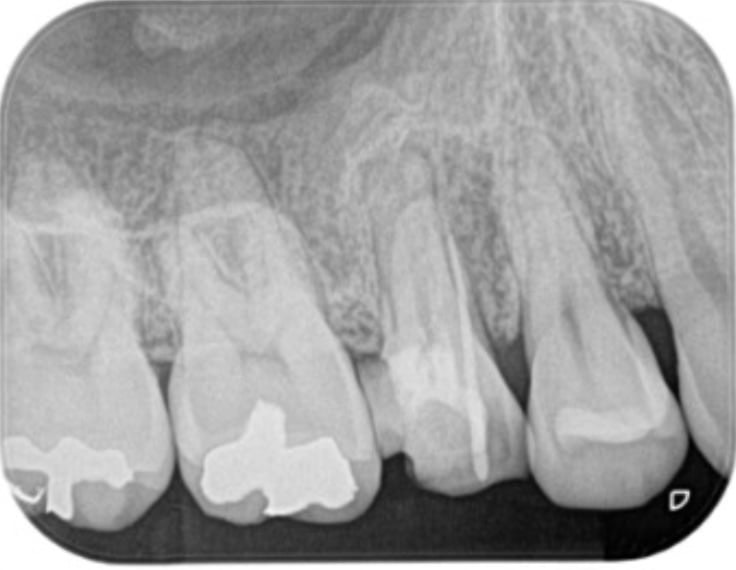

支台築造(根管治療が終了してから被せる前の土台)

すでに感染している。もしくは被せ直しをするために念のため内部を再度綺麗にする治療です。

当院で支台築造を行う場合は根管治療後可能な限り早くラバーダム下で無菌的処置環境を徹底して行います。 紹介元の歯科医院で支台築造を行なっても問題ありませんが、その際は連絡(報告書やEメールなど)し連携に配慮いたします。